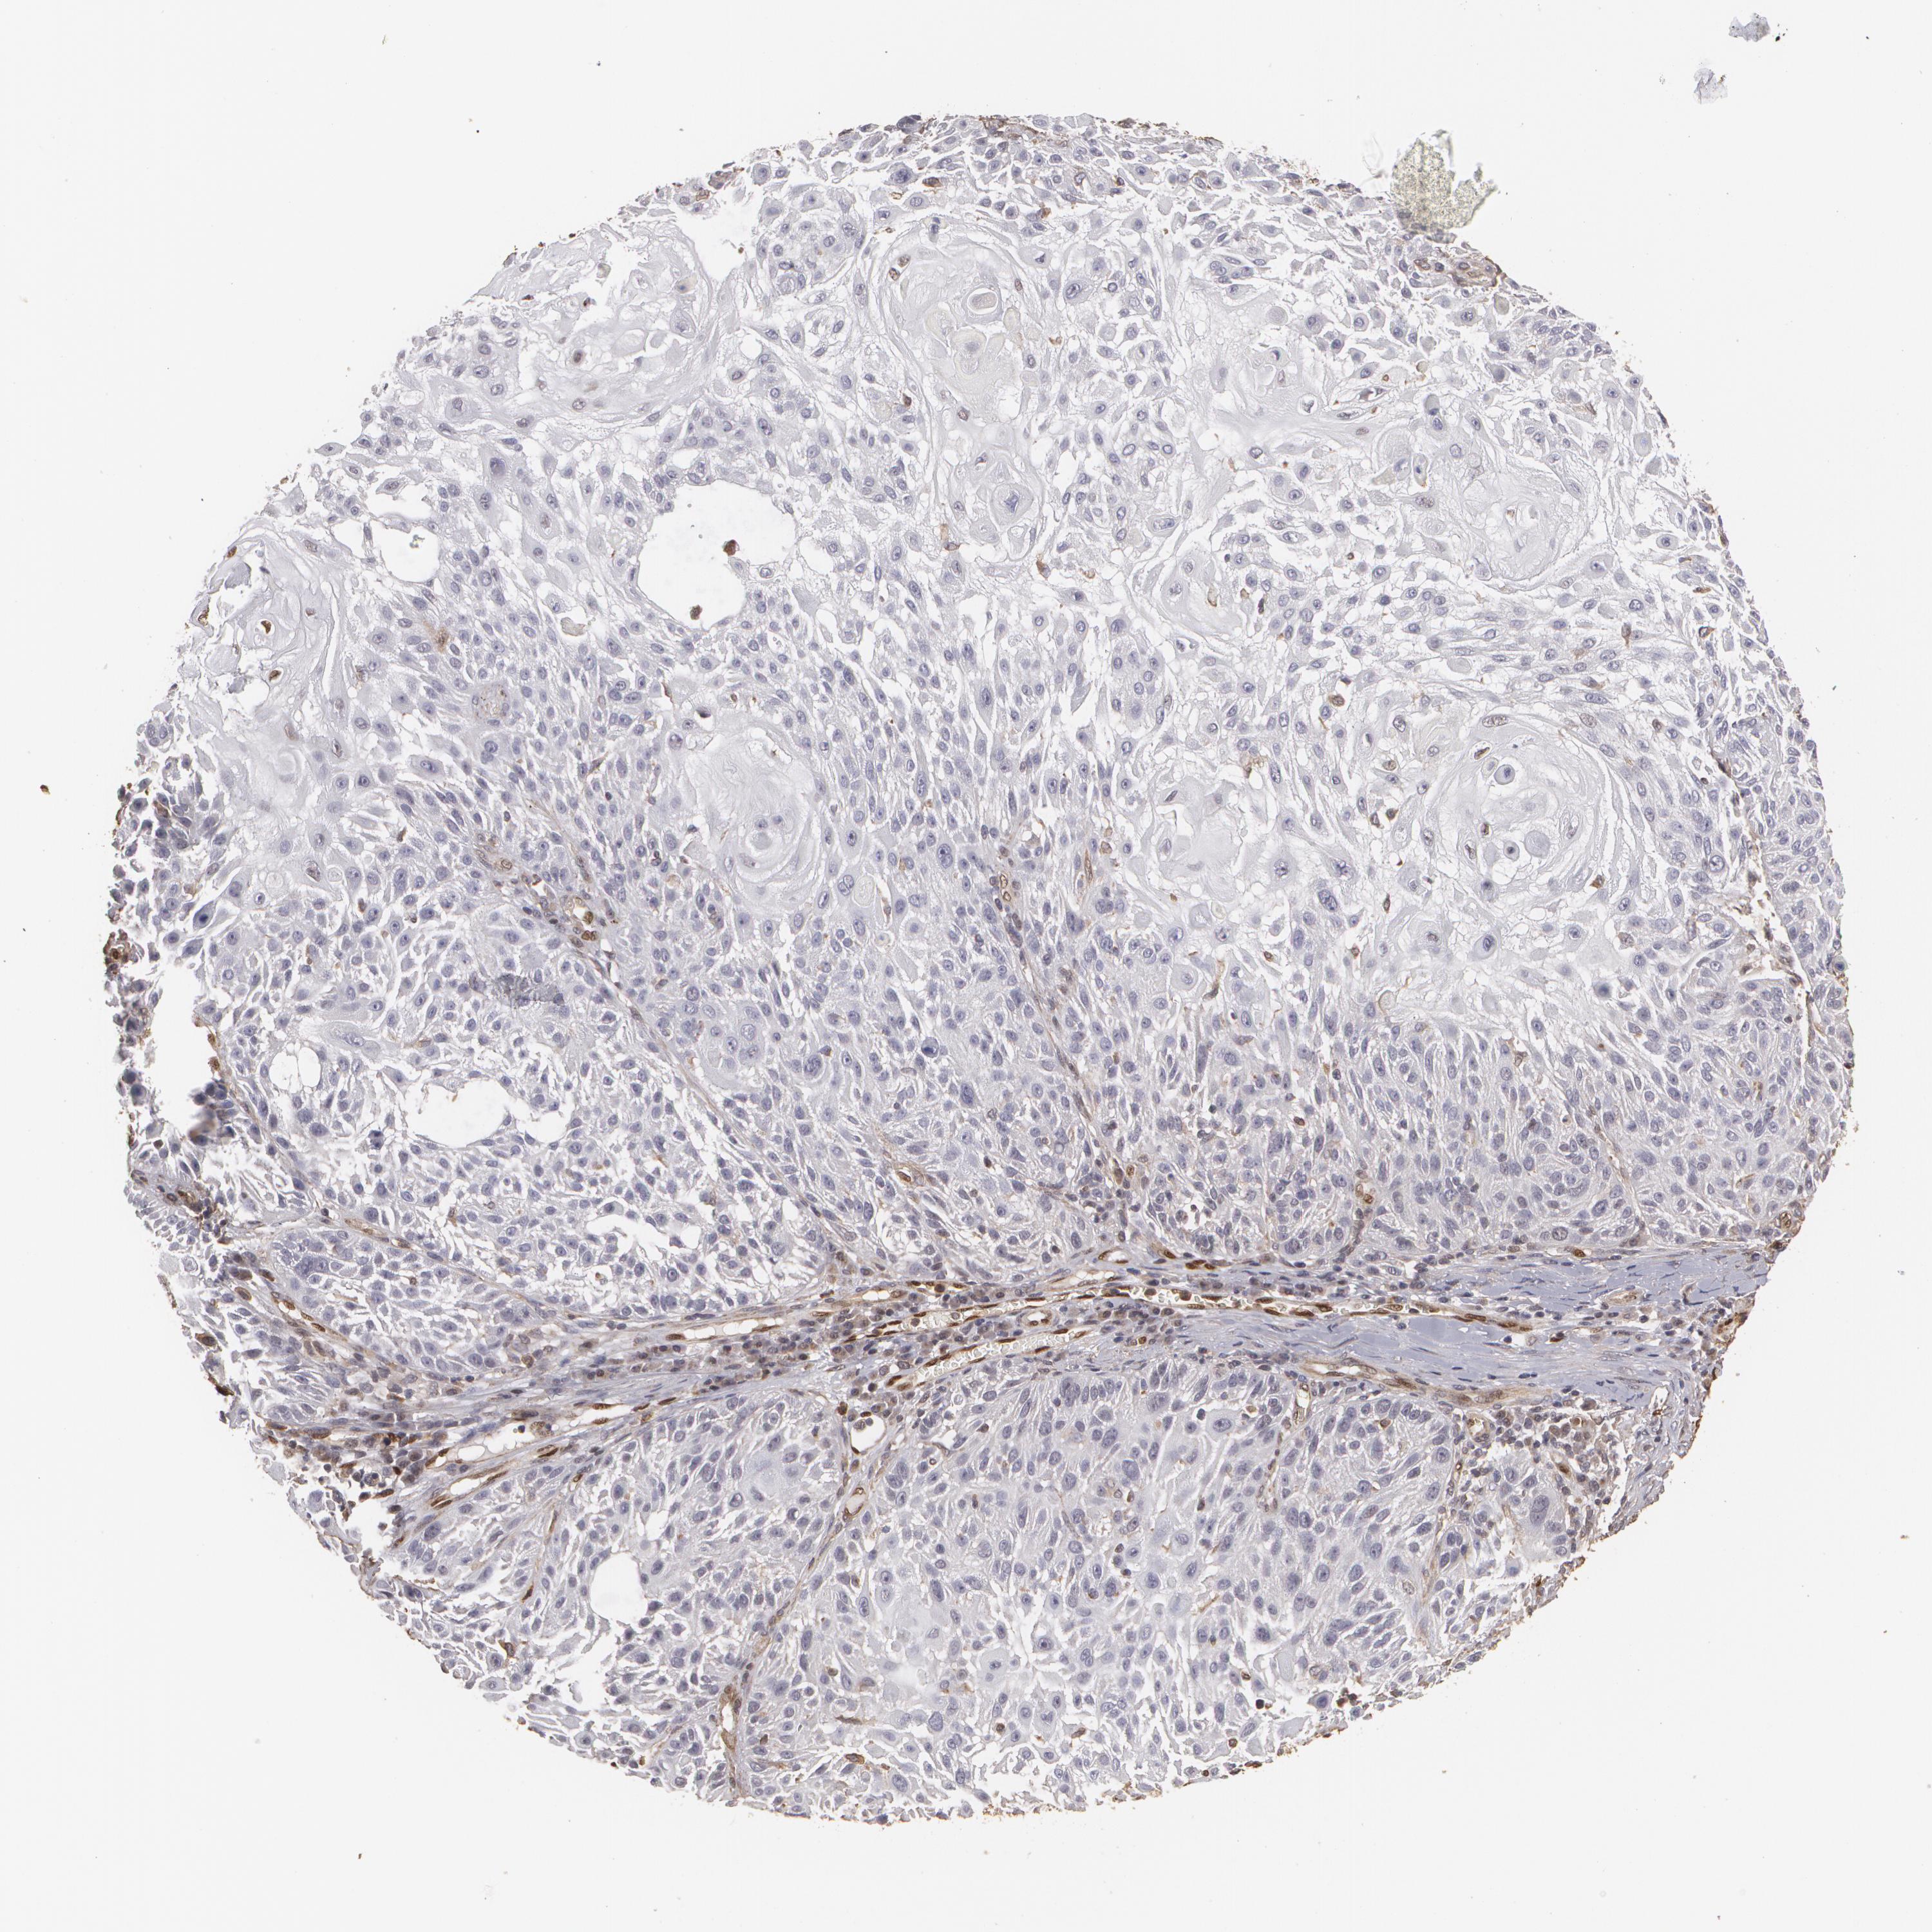

CANCER SKIN CANCER Show tissue menu

SKIN CANCER - Protein expressioni

A mouse-over function shows sample information and annotation data. Click on an image to view it in a full screen mode. Samples can be filtered based on level of antibody staining by selecting one or several of the following categories: high, medium, low and not detected. The assay and annotation is described here.

Antibody stainingi

Antibody staining in the annotated cell types in the current human tissue is reported as not detected, low, medium, or high, based on conventional immunohistochemistry profiling in selected tissues. This score is based on the combination of the staining intensity and fraction of stained cells.

Each image is clickable and will lead to virtual microscopy that enables deeper exploration of all samples and also displays staining intensity scores, fraction scores and subcellular localization as well as patient and tissue information for each sample.

Antibody HPA001600

Staining

High

Medium

Low

Not detected

Intensity

Strong

Moderate

Weak

Negative

Quantity

>75%

75%-25%

<25%

None

Location

Nuclear

Cytoplasmic/membranous

Cytoplasmic/membranous,nuclear

Squamous cell carcinoma, NOS

Basal cell carcinoma